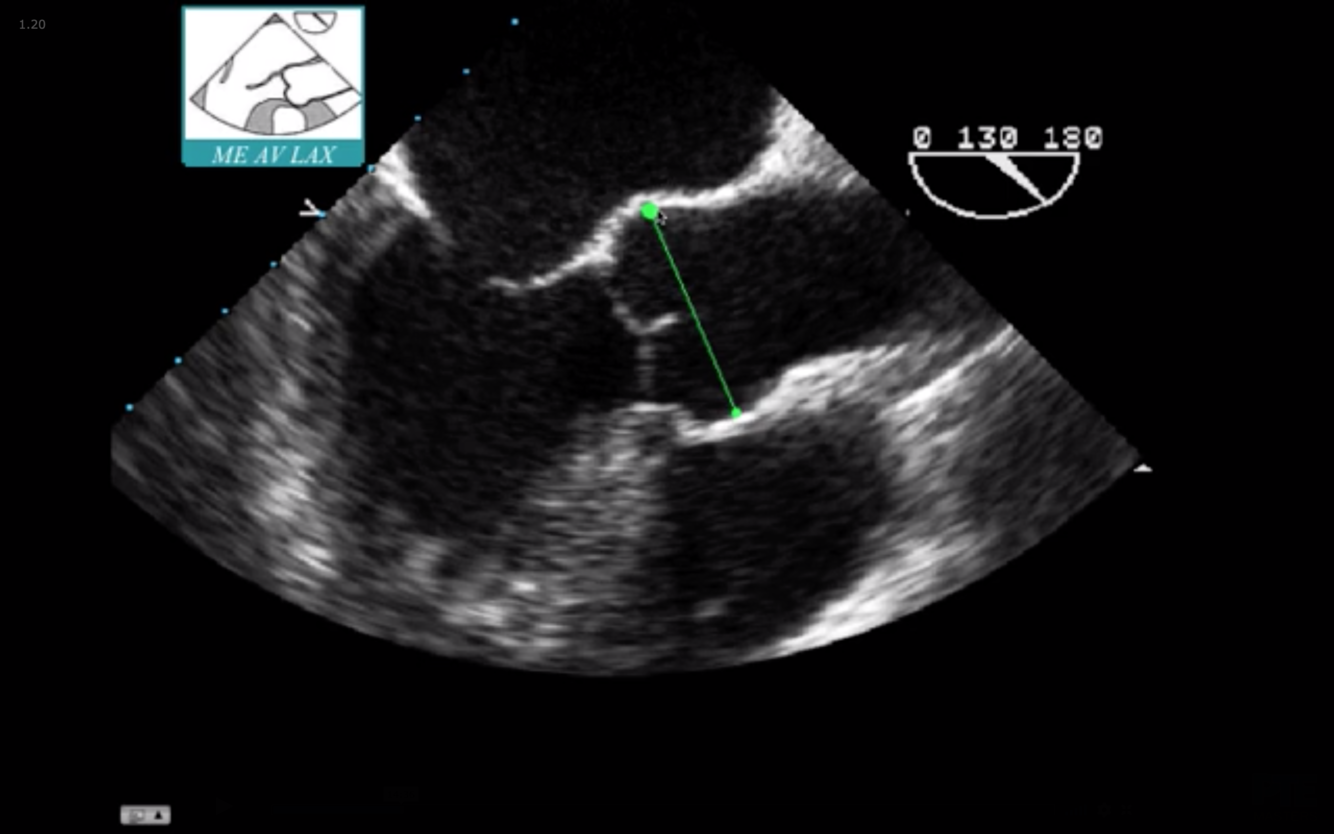

What is the measurement seen here?

Sinus of Valsalva

What is the blue arrow indicating?

Sinotubular Ridge or Sinuotubular Junction

What is seen in red?

Aortic Annulus

What is the normal size of the Aortic Root in an adult?

What measurement is termed dilated?

Normal = < 40 mm (4.0 cm)

Dilated = >40 mm

What TEE view is utilized to assess AI Jet / LVOT diameter to assess quantitatively for AI?

Mid Esophageal Aortic Valve Long Axis